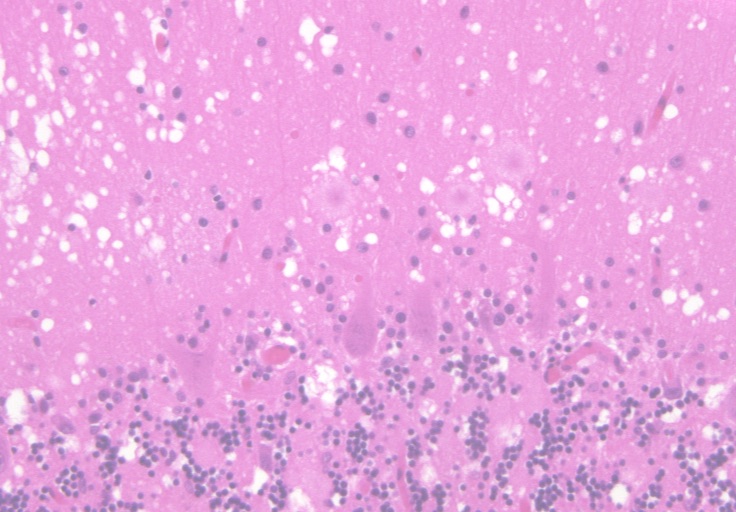

2. Cerebellum

Cerebellum

H&E